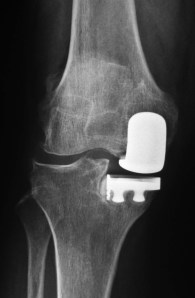

Mdm Tan was offered a partial knee replacement surgery to treat her condition.

Mdm Tan was able to stand up on the 1st day after surgery. She started to walk with the help of a walking frame on the 2nd day after surgery. She went home on the 3rd day after the surgery.